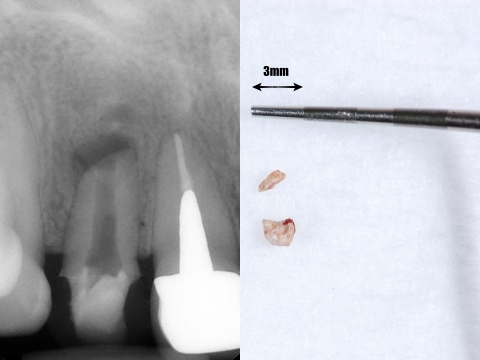

今回歯の上部は健全な部分がたくさん残っているので、上から直径3ミリほどの小さな穴を開けそこから、根の内部の吸収部を除去しようと試みました。

すると吸収部にはただ単に歯が溶けているのではなく、肉芽という歯茎の一部が入り込んでしまっているので、穴を開けた瞬間に血が噴き出してきて、血まみれで中を見るのが困難な状態でした。

そこで肉芽を様々な器具や技で除去をし、出血を止め薬剤で消毒しました。

言葉で書くのは簡単ですが、これには非常に時間がかかりとても困難な治療でした。そこにMTAセメントを用い、根の先端の方(赤矢印)と吸収部(黄色矢印)を同時に埋めました。